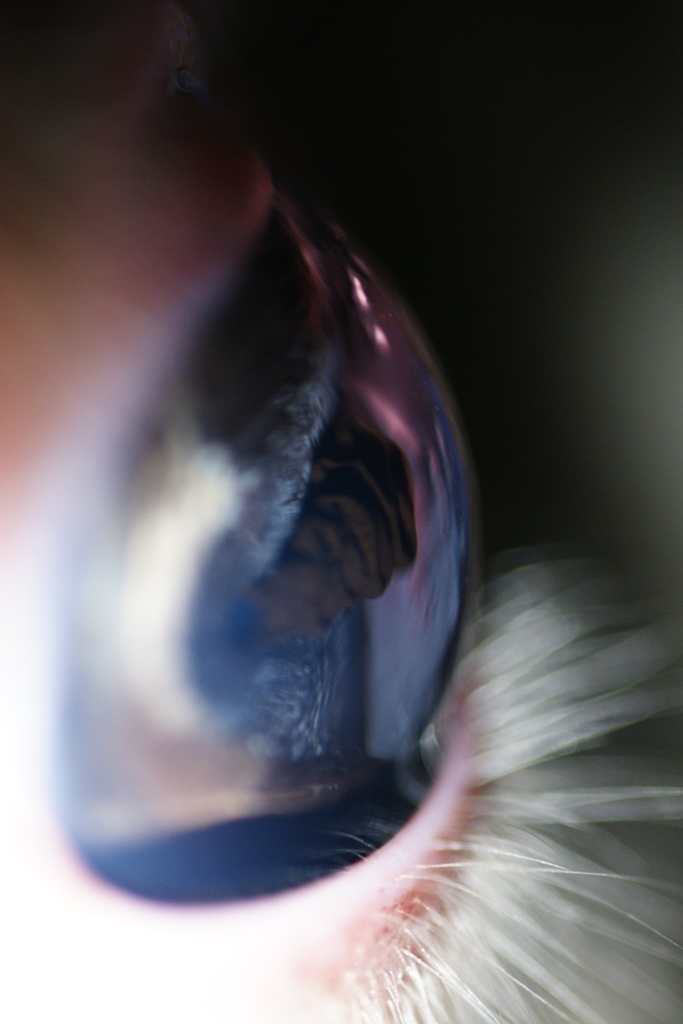

Uvéite antérieure exsudative chez un chat (tous les petits amas sont de la fibrine et traduisent l'inflammation)

- 64533 (353.48 Kio) Consulté 2735 fois